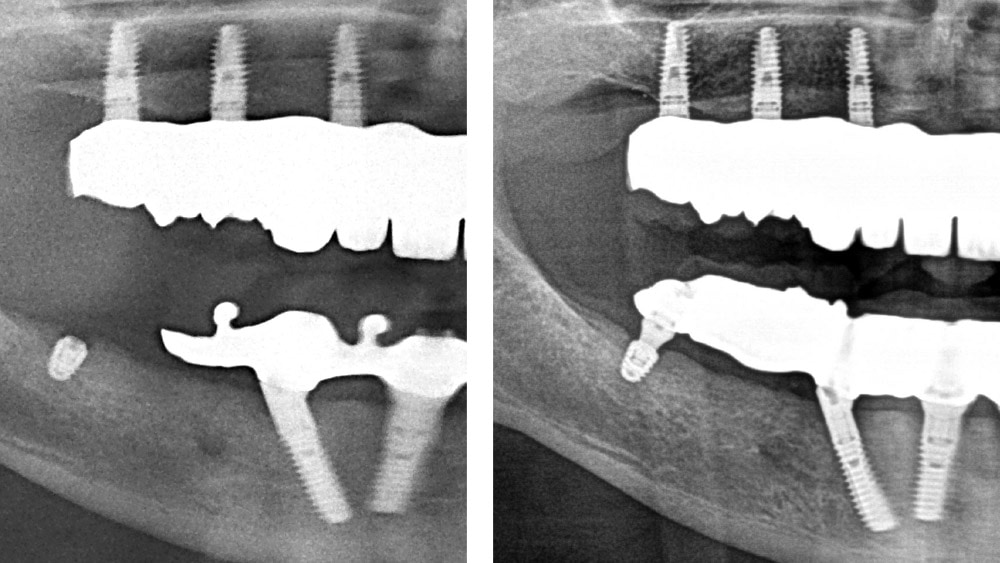

copaSKY TiSi.snap, sinir veya sinüs üzerindeki posteriorlarda sınırlı kemik yüksekliği olan restorasyonlarda, çıkarılabilir restorasyonları desteklemek için ideal bir çözümdür. Ön bölgede miniSKY ve TiSi.snap ile birlikte ideal. Protez üzerinde sabitleme: